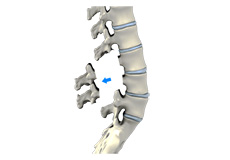

Lumbar Laminectomy

Lumbar laminectomy is a spinal surgery to relieve excess pressure on the spinal cord or nerves within the spinal canal in the lumbar or lower back region. The pressure may be caused by bony overgrowths, herniated discs, injury, tumors, or narrowing of the spinal canal resulting in painful symptoms affecting a person’s ability to perform normal day to day activities.